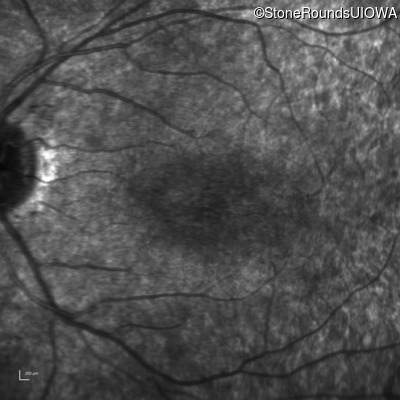

Age at visit: 7 years

OD OS

This 7 year old girl has had very poor vision in dim light and slightly subnormal acuity her entire life.